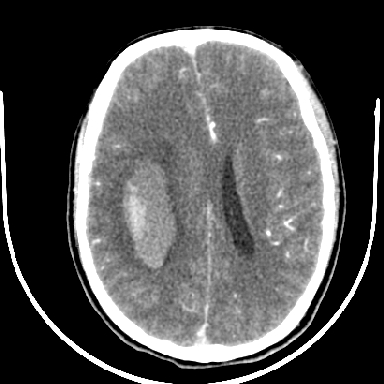

标题: CT6056:脑出血(血管畸形?)

m 40突发头痛左侧偏瘫3小时

考虑高血压性脑出血,依据:

1是高血压性脑出血的好发部位,形态呈肾形,是高血压性脑出血的常见形状

2增强时占位效应加重了,考虑出血还没有停止

3病灶周围水肿不是太厉害,一般肿瘤出血水肿多非常明显

4病灶周围的‘软组织’影没有明显的强化

5至于脑血管畸形引起的出血,暂时没有看到明显的畸形血管影,也不太支持

支持右侧基底节脑出血

右侧基底节区脑出血.

支持右侧基底节区(主要为外囊区)原发性脑出血。

另附部分资料:“血液溢出血管外形成血肿,其内含有大量血红蛋白、血浆白蛋白,球蛋白,因这些蛋白对x线的吸收系数高于脑质,故ct呈现高密度阴影,ct值达40~90h,最初高密度灶呈非均匀一致性,中心密度更高,新鲜出血灶边缘不清。基底节区血肿多为“肾”型,内侧凹陷,外侧膨隆,因外侧裂阻力较小,故向外凸,其它部位血肿多呈尖圆形或不规则形”